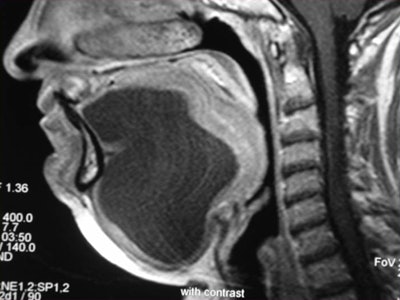

Contrast-enhanced coronal and sagittal T1-weighted images show a large, hourglass-shaped midline cystic lesion in the floor of the mouth splitting the genioglossus muscles. The diagnosis is a dermoid cyst. Images courtesy of Dr. Alexandra Borges.

Whenever imaging a malignancy, the full extent of the neck should be imaged for nodal staging. Bone windows are required for all cases of cancer staging and whenever dentomaxillary pathology is suspected.

Finally, she emphasized that when using MRI, it is crucial to instruct a patient not to swallow and to breathe quietly during the entire examination. The use of surface coils can be very helpful for the imaging of superficially located lesions such as the parotid and submandibular glands and the floor of the mouth.